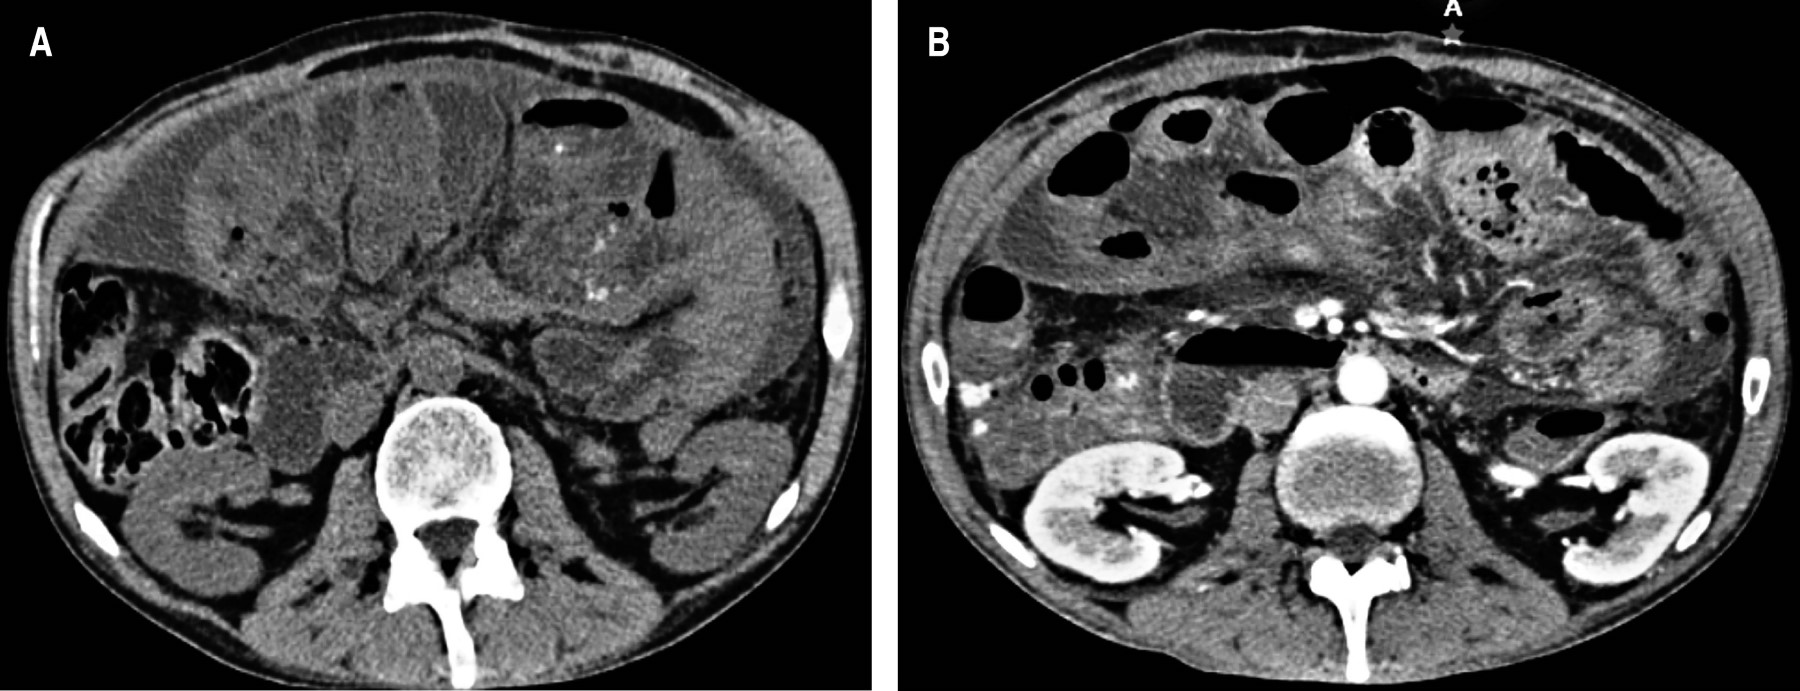

He was admitted to the hospital, and due to suspicion of occlusion secondary to surgical adhesions, conservative management was decided based on intestinal rest, a nasogastric tube placement, and crystalloid fluid therapy; however, due to persistent symptoms and increased abdominal pain, a simple abdominopelvic CT scan was requested showing distension of the small bowel loops, with maximum dilatation in the terminal ileum, as well as wall edema and concentric striations due to probable intussusception (Figure 1).

As mentioned in the clinical case, the first suspicion regarding a semiology of this type is intestinal occlusion, which is why conservative management was decided; however, due to persistent symptoms and increased abdominal pain, a simple abdominopelvic CT scan was requested as indicated by the literature, which guided us to the diagnosis due to the finding of the characteristic radiological image, the cocoon sign, giving rise to surgical treatment in which complete resection of the peritoneal capsule was performed; after this, the histopathological diagnosis confirmed what has already been described by several authors concerning the histology and composition of the capsule.

Sclerosing encapsulating peritonitis or abdominal cocoon is a rare cause of intestinal occlusion characterized by the formation of a diffuse fibro-collagenous peritoneum membrane. The imaging study of choice is a contrasted CT scan. The typical radiological finding is the presence of a conglomerate of small loops covered by an enveloping and thickened peritoneum, the cocoon sign.